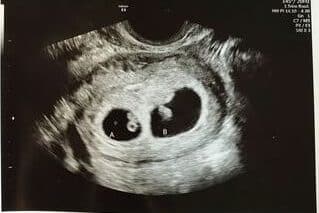

High levels of hCG do not necessarily mean that you will have twins. You can also have high levels of hCG with a singleton pregnancy. The chances of having twins increase with higher levels of hCG, but hCG on its own is not an accurate predictor. The only way to confirm that you’re having twins is to have an ultrasound as early as 6 weeks of pregnancy.

In pregnancies with twins, it’s not uncommon for hCG levels to be higher than those in singleton pregnancies, but relying solely on hCG levels is not a definitive method for determining the number of fetuses.

To determine the accurate number of fetuses and ensure the overall health of the pregnancy, ultrasound remains the most reliable diagnostic tool. If you suspect you are pregnant with twins or have concerns about your pregnancy, it is crucial to consult with your healthcare provider.